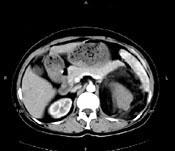

问题 女,64岁,左侧腰部胀痛,行CT扫描,下列说法正确的是 ( )

选项 A、考虑为左侧肾上腺来源的髓样脂肪瘤 B、考虑为腹膜后来源的脂肪肉瘤 C、该病灶密度不均匀,其内可见脂肪密度影,且呈不均匀强化 D、考虑为左肾来源的血管平滑肌脂肪瘤 E、左肾区可见一巨大的占位性病灶,境界较清楚,胰腺尾部受压向前推移

答案 CDE